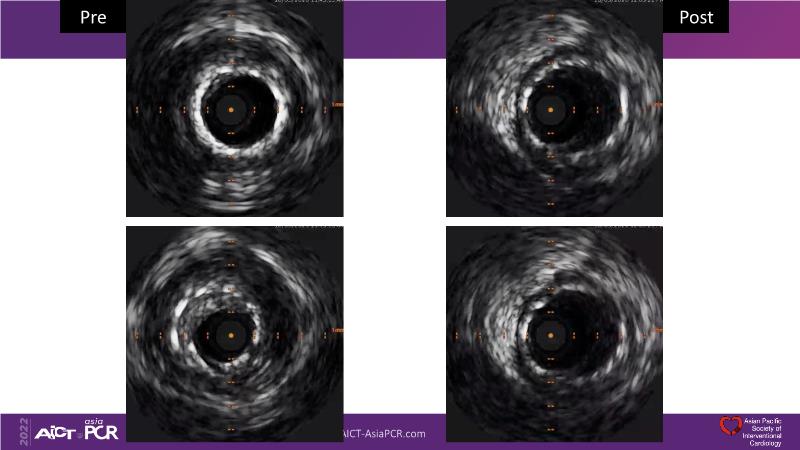

Consult this session to understand the technology and scientific evidence of the novel sirolimus drug-coated balloon, to learn its utility for PCI in a variety of lesion and patient subsets and to understand the evidence and outcomes in real-world patients.

- To understand the technology and scientific evidence of the novel sirolimus drug-coated balloon (SDCB)

- To learn the utility of the DCB for PCI in a variety of lesion and patient subsets

- To understand the evidence and outcomes of this DCB in real world patients